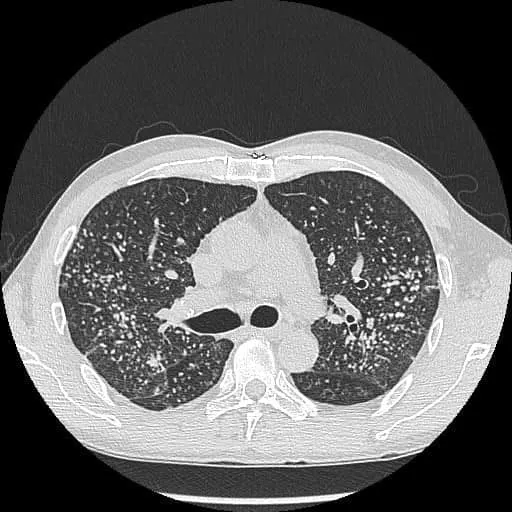

蘇一峰在臉書發文表示,一名40歲男患者不抽菸,但喘了幾個月因此到胸腔科治療,結果發現他十隻手指幾乎都是杵狀指,因此也安排他照X光,「X光就看到滿天星的肺結節,成千上萬顆肺結節,讓密集恐懼症的人頭皮發麻」。

40歲男X光照出成千上萬顆肺結節。翻攝蘇一峰臉書

40歲男胸部X光。翻攝蘇一峰臉書